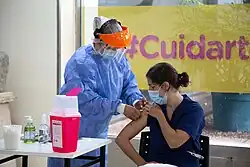

Vaccination campaign

Vaccination against COVID-19 began in Argentina on 29 December 2020 aiming at health professionals.[157] During the first week, 39,599 doses were applied to health professionals.[158]

On 18 February 2021, vaccination on citizens aged over 70 began in the Province of Buenos Aires. Schools, among other sites, were used as temporary vaccination centres.[159]

On 18 November 2021, health minister Vizzotti said that there was "sufficient stock" to vaccinate all the population with a booster dose. The campaign of the booster dose began in late October 2021, with people over the age of 70 and health personnel; and those above the age of 50 who completed their two doses with Sinopharm.[160][161]